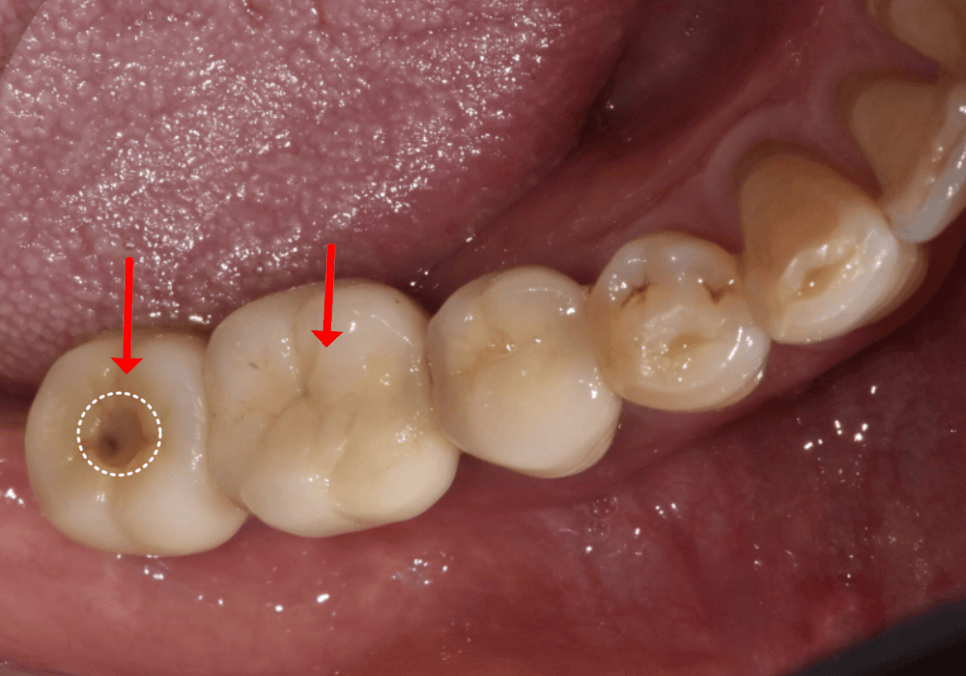

그런데,

여기서 예상치 못한 난관에 부딪혔습니다.

환자분의 기존 보철물이

'시멘트(Cement) 타입'이었기 때문입니다.

임플란트 보철을 만드는 방식은

크게 두 가지가 있는데,

이 둘은 유지 보수 면에서 큰 차이가 있습니다.

① 시멘트 타입 (Cement Type)

마치 자연치아처럼 뚜껑을 덮고,

치과용 강력 접착제로 '딱' 붙여버리는 방식입니다.

장점 : 나사 구멍이 없어서 외관상 아주 깔끔하고 예쁩니다. 씹는 면이 매끈해서 음식물이 끼거나 걸리는 느낌도 덜하죠.

단점 : 수리가 매우 어렵습니다. 숨겨진 나사 구멍을 찾느라 멀쩡한 보철을 뚫어야 하거나, 최악의 경우 보철물을 통째로 뜯어내야 합니다.

안타깝게도 환자분은

'문'이 없는 1번(시멘트 타입)이었습니다.

단단한 도자기를 무리해서

뚫다간 보철만 망가지고

환자분 고생만 길어지기에,

결국 상의 끝에 기존 보철을 뜯어내기로

결정했습니다.